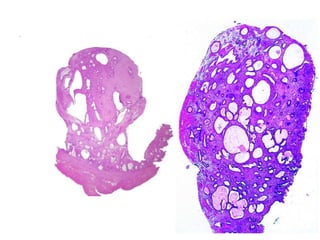

Teratoma

Teratomas maduros (benignos)

Teratoma imaturo

BlastemaNeuroectoderma

Tumores germinativos malignos

Disgerminoma Tu seio endodérmico

Carcinoma embrionário Coriocarcinoma